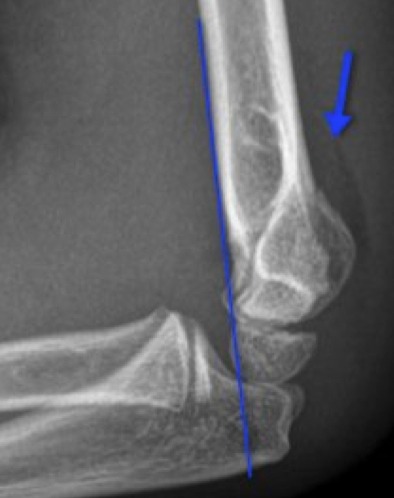

Subtle radiographic findings

- The Type II and Type III fractures are often no-brainers… bone looks broke!

- Type I can be very subtle… so look for:

- Displaced Anterior Fat Pad (Sail Sign)

- Any Posterior Fat Pad

- Anterior Humeral Line not intersecting the middle third of the capitellum.

- Radiocapitellar line not interesting the middle third of the capitellum.